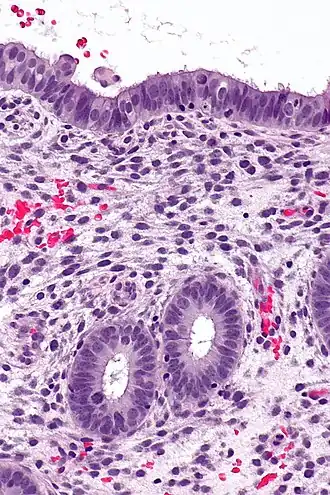

![]() Endometrium in the proliferative phase | |

Structure

The endometrium consists of a single layer of columnar epithelium plus the stroma on which it rests. The stroma is a layer of connective tissue that varies in thickness according to hormonal influences. In the uterus, simple tubular glands reach from the endometrial surface through to the base of the stroma, which also carries a rich blood supply provided by the spiral arteries. In women of reproductive age, two layers of endometrium can be distinguished. These two layers occur only in the endometrium lining the cavity of the uterus, and not in the lining of the fallopian tubes where a potentially life-threatening ectopic pregnancy may occur nearby.[4][5]

It is possible to identify the phase of the menstrual cycle by reference to either the ovarian cycle or the uterine cycle by observing microscopic differences at each phase—for example in the ovarian cycle:

| Phase | Days | Thickness | Epithelium |

|---|---|---|---|

| Menstrual phase | 1–5 | Thin | Absent |

| Follicular phase | 5–14 | Intermediate | Columnar |

| Luteal phase | 15–27 | Thick | Columnar. Also visible are arcuate vessels of uterus |

| Ischemic phase | 27–28 | Columnar. Also visible are arcuate vessels of uterus |